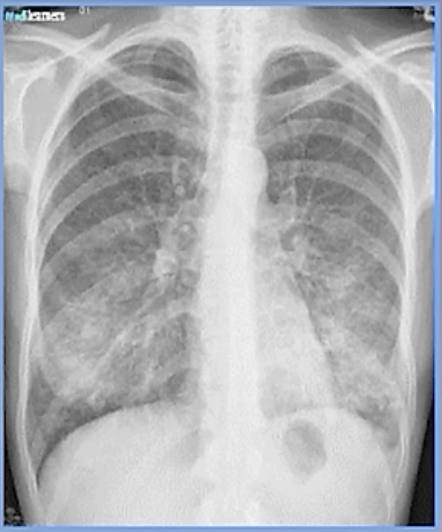

21

Q

Imagen de neumonia necrotizante

A

se ven cavitaciones y la da S.aureus o TB